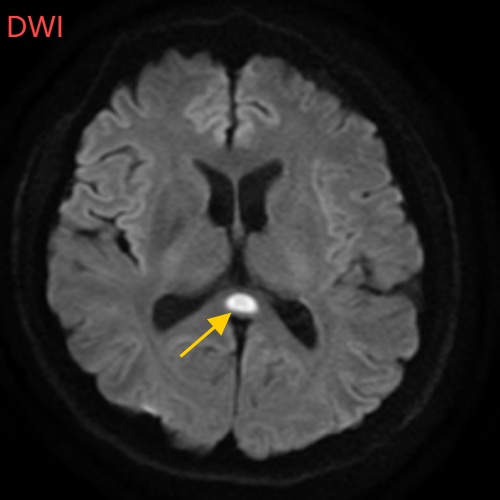

小董的影像结果显示,胼胝体压部发生病变

胼胝体压部("压部")是大脑里的“视觉总监”,眼睛所看到的信息传送到大脑后,由它负责反应整合成图像在脑海中呈现。“压部”发生病变后,就像电视机信号接收不良,屏幕出现雪花一样,眼睛视物就会受到影响。除了“压部”,胼胝体的其他部位也有病变,所以小董才会出现幻听、手抖等症状。

经过一周治疗,小董的胼胝体压部病变明显好转